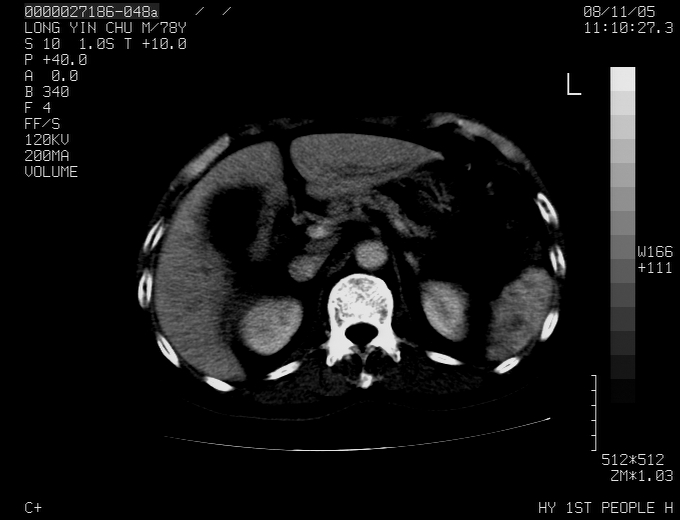

标题: CT16532:M78Y,肝脏病变,请会诊 [打印本页]

标题: CT16532:M78Y,肝脏病变,请会诊

腹胀,腹痛就诊,男性,78岁,外院b超未见异常。

肝ca,脾肾转移

考虑弥漫性肝癌并脾及双肾转移.双侧胸水.

图片质量欠佳:多考虑:左侧肾癌。脾脏转移!胸膜转移!

肝脾肾转移瘤可能性大,左肾不除外梗塞,双侧胸水

考虑弥漫性肝癌并脾及双肾转移,双侧胸水。

考虑肝癌并双肾及脾脏转移;双侧胸腔积液。